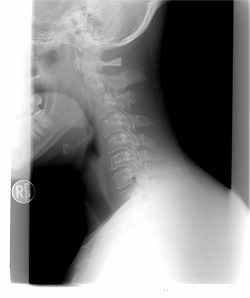

脊髄損傷の症状固定のタイミングについて

交通事故による脊髄損傷の治療の上で、必ずと言っていいほど問題となるのが症状固定のタイミングです。

ですが、脊髄損傷は再生不可能な脊髄が断裂している状態ですので、交通事故以前の状態に戻ることはありません。

脊髄損傷は交通事故にあった直前は回復するように治療がされますが、「これ以上身体機能の回復が認められない」とみなされると、リハビリやケアを中心としたものに変わっていきますが、治療も並行して行われることも多くあります。

そのため、脊髄損傷の症状固定を決める時期は、交通事故の後遺症の中でも難しいと言えます。